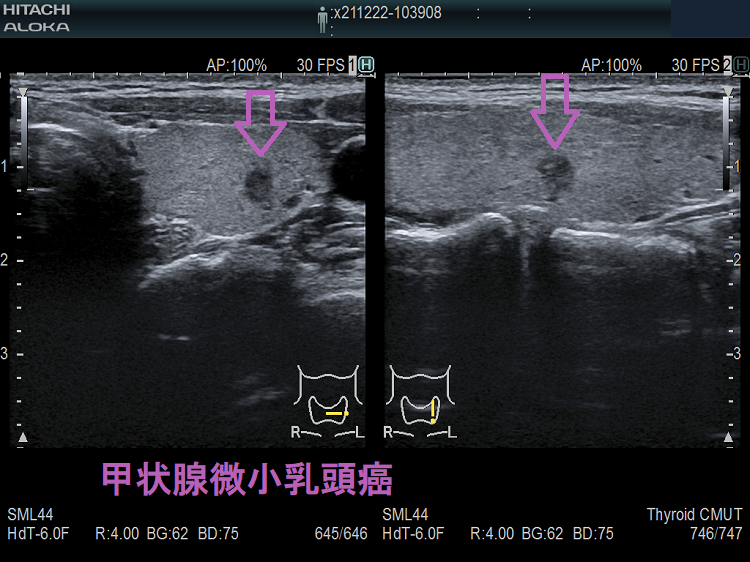

甲状腺微小乳頭癌は超音波エコー検査でどう見えるか①極めて低エコー(不整形、境界不明瞭、辺縁粗雑)で橋本病(慢性甲状腺炎)の破壊による変性と鑑別難②環状高エコー被膜③石灰化(微細石灰化・斑点状・卵殻状石灰化は通常型と同じ、破片状・塊状石灰化が多い)。甲状腺微小乳頭癌で反回神経浸潤(Ex1,Ex2)が術前・術中に見つかるのは、腫瘍が背側かつ気管寄りの場合。甲状腺超音波(エコー)では腺腫様結節にしか見えず、エラストグラフィーで軟らかく、10mmに満たないが穿刺細胞診すると甲状腺微小乳頭癌の事がある。女性の30人に1人の割合で甲状腺乳頭癌が存在。

- 最も一般的なのは、真っ黒な(極めて低エコー)、いびつな形(きれいな円形・楕円形をしていない、不整な形)をした、境界がはっきりしない(境界不明瞭)、辺縁粗雑な腫瘤

[以上の条件を満たす10mm未満の腫瘤は、不整な低エコー領域として見えるため、特に橋本病(慢性甲状腺炎)では甲状腺組織の破壊による変性と鑑別が難しい。]

- 1cm以上の甲状腺乳頭癌と甲状腺微小乳頭癌で、石灰化率に有意差はないとされます[Exp Ther Med. 2014 Oct;8(4):1335-1339.]。しかし、甲状腺微小乳頭癌の石灰化パターンは、1cm以上の甲状腺乳頭癌とやや異なります。微細石灰化・斑点状石灰化・卵殻状石灰化の頻度は1cm以上の甲状腺乳頭癌と同じですが、甲状腺微小乳頭癌では破片状・塊状石灰化の頻度が多い。